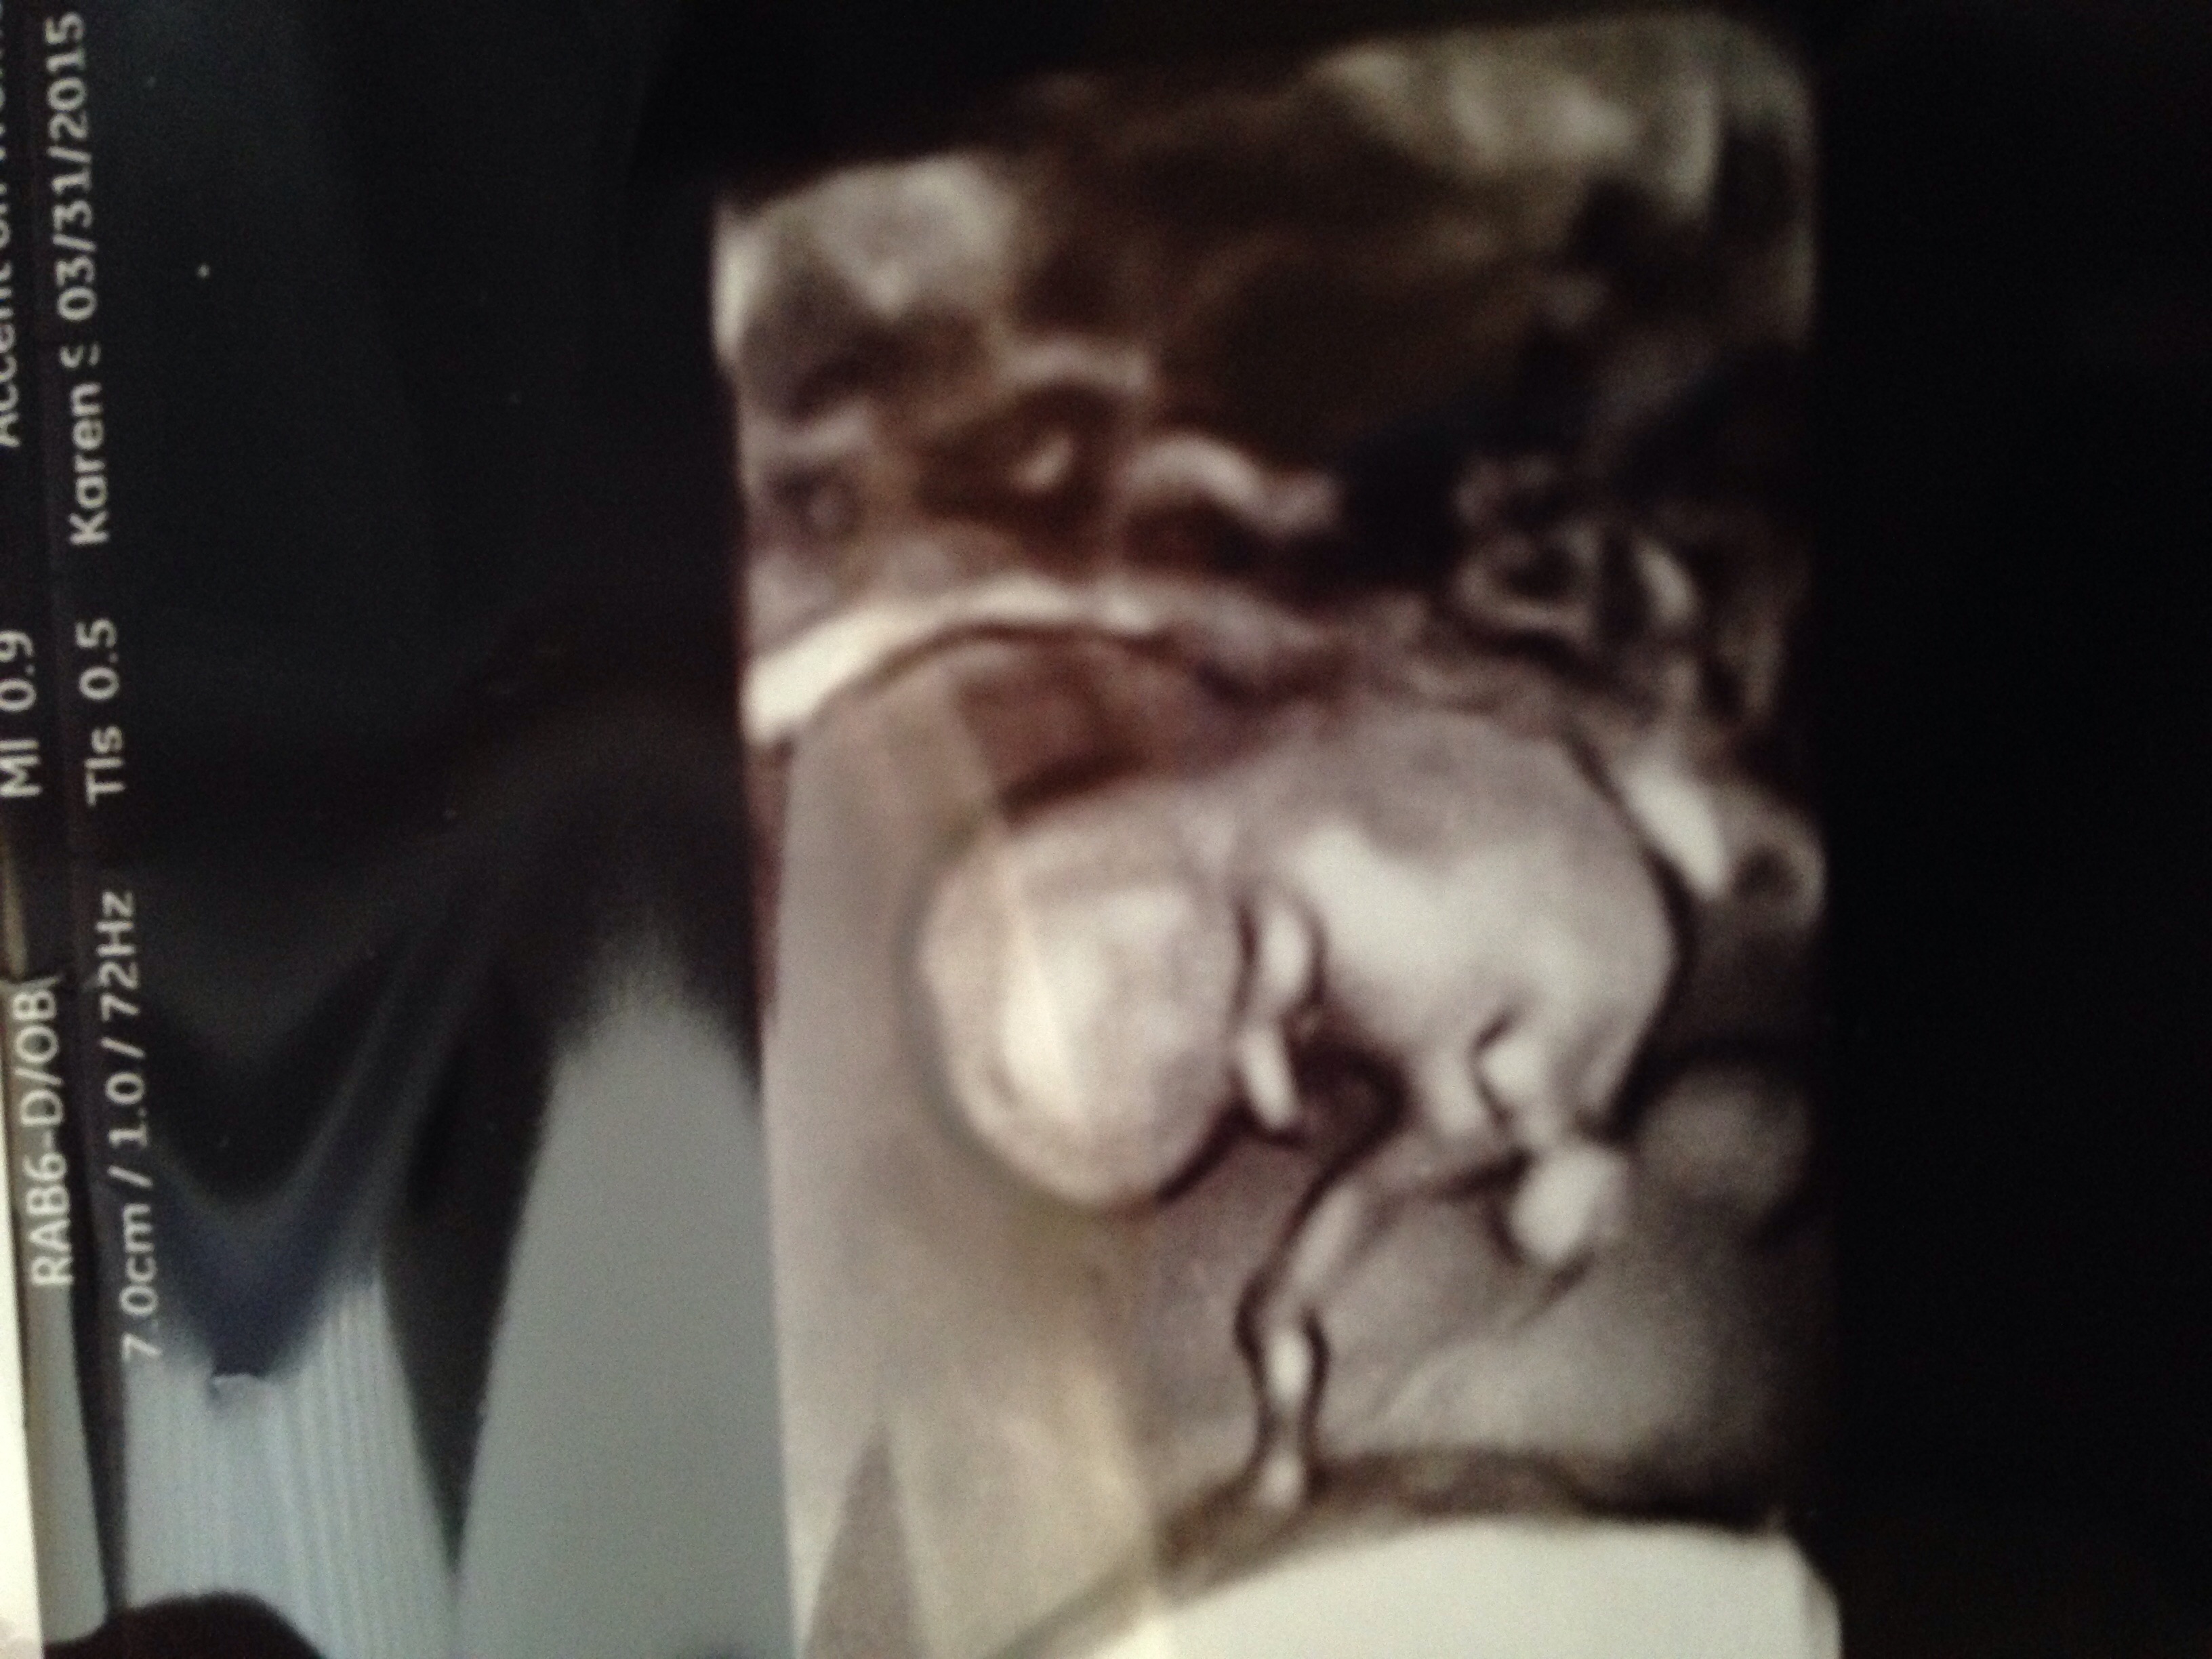

so we get to find out the sex of our little one next week but I'm being impatient and have almost convinced myself that I see boy parts in this ultrasound pic. So tell me what you guys think??

• Oh right I should say I was 10weeks at this point.. So I am crazy? Haha

• These look like very early ultrasound photos. How many weeks were you? If this was early I wouldn't guess sex based off of them. Boys and girls look the same in the beginning.

• External genitals finish developed at 15-16 weeks, so it was probably too early in those photos ;) I always feel bad when these posts pop up because we all want to give our fellow preggo ladies hope or comfort, but sometimes, it's just not in the cards. I had my anatomy scan at the beginning of May (that they'd accidentally scheduled too early) so I learned the gender, but not much else, so I know how excited you are!!